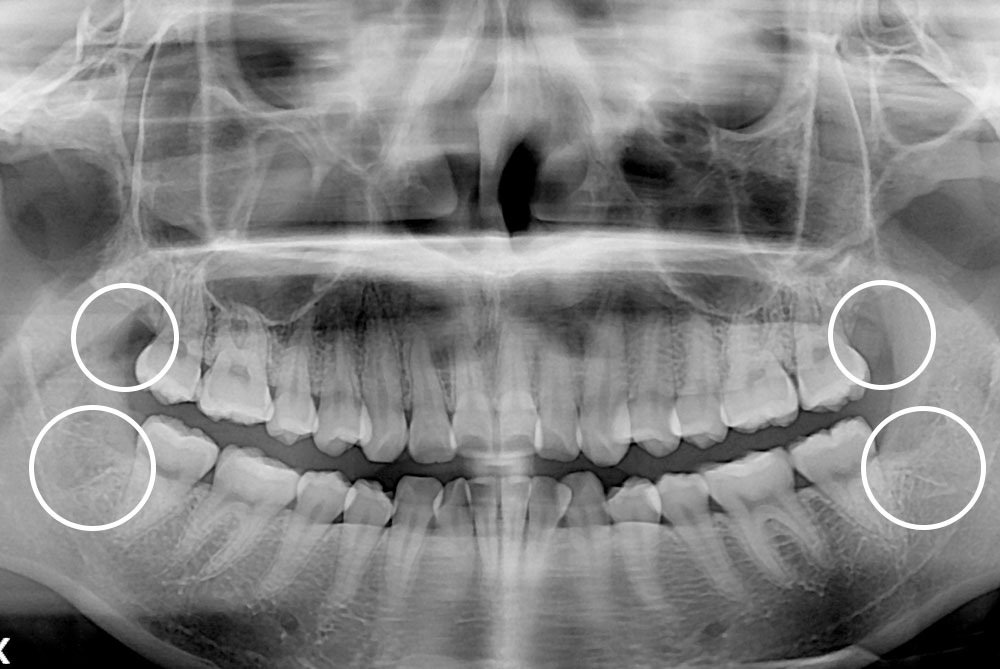

[사랑니] 매복 사랑니 발치

치료후 : 2019-09-26